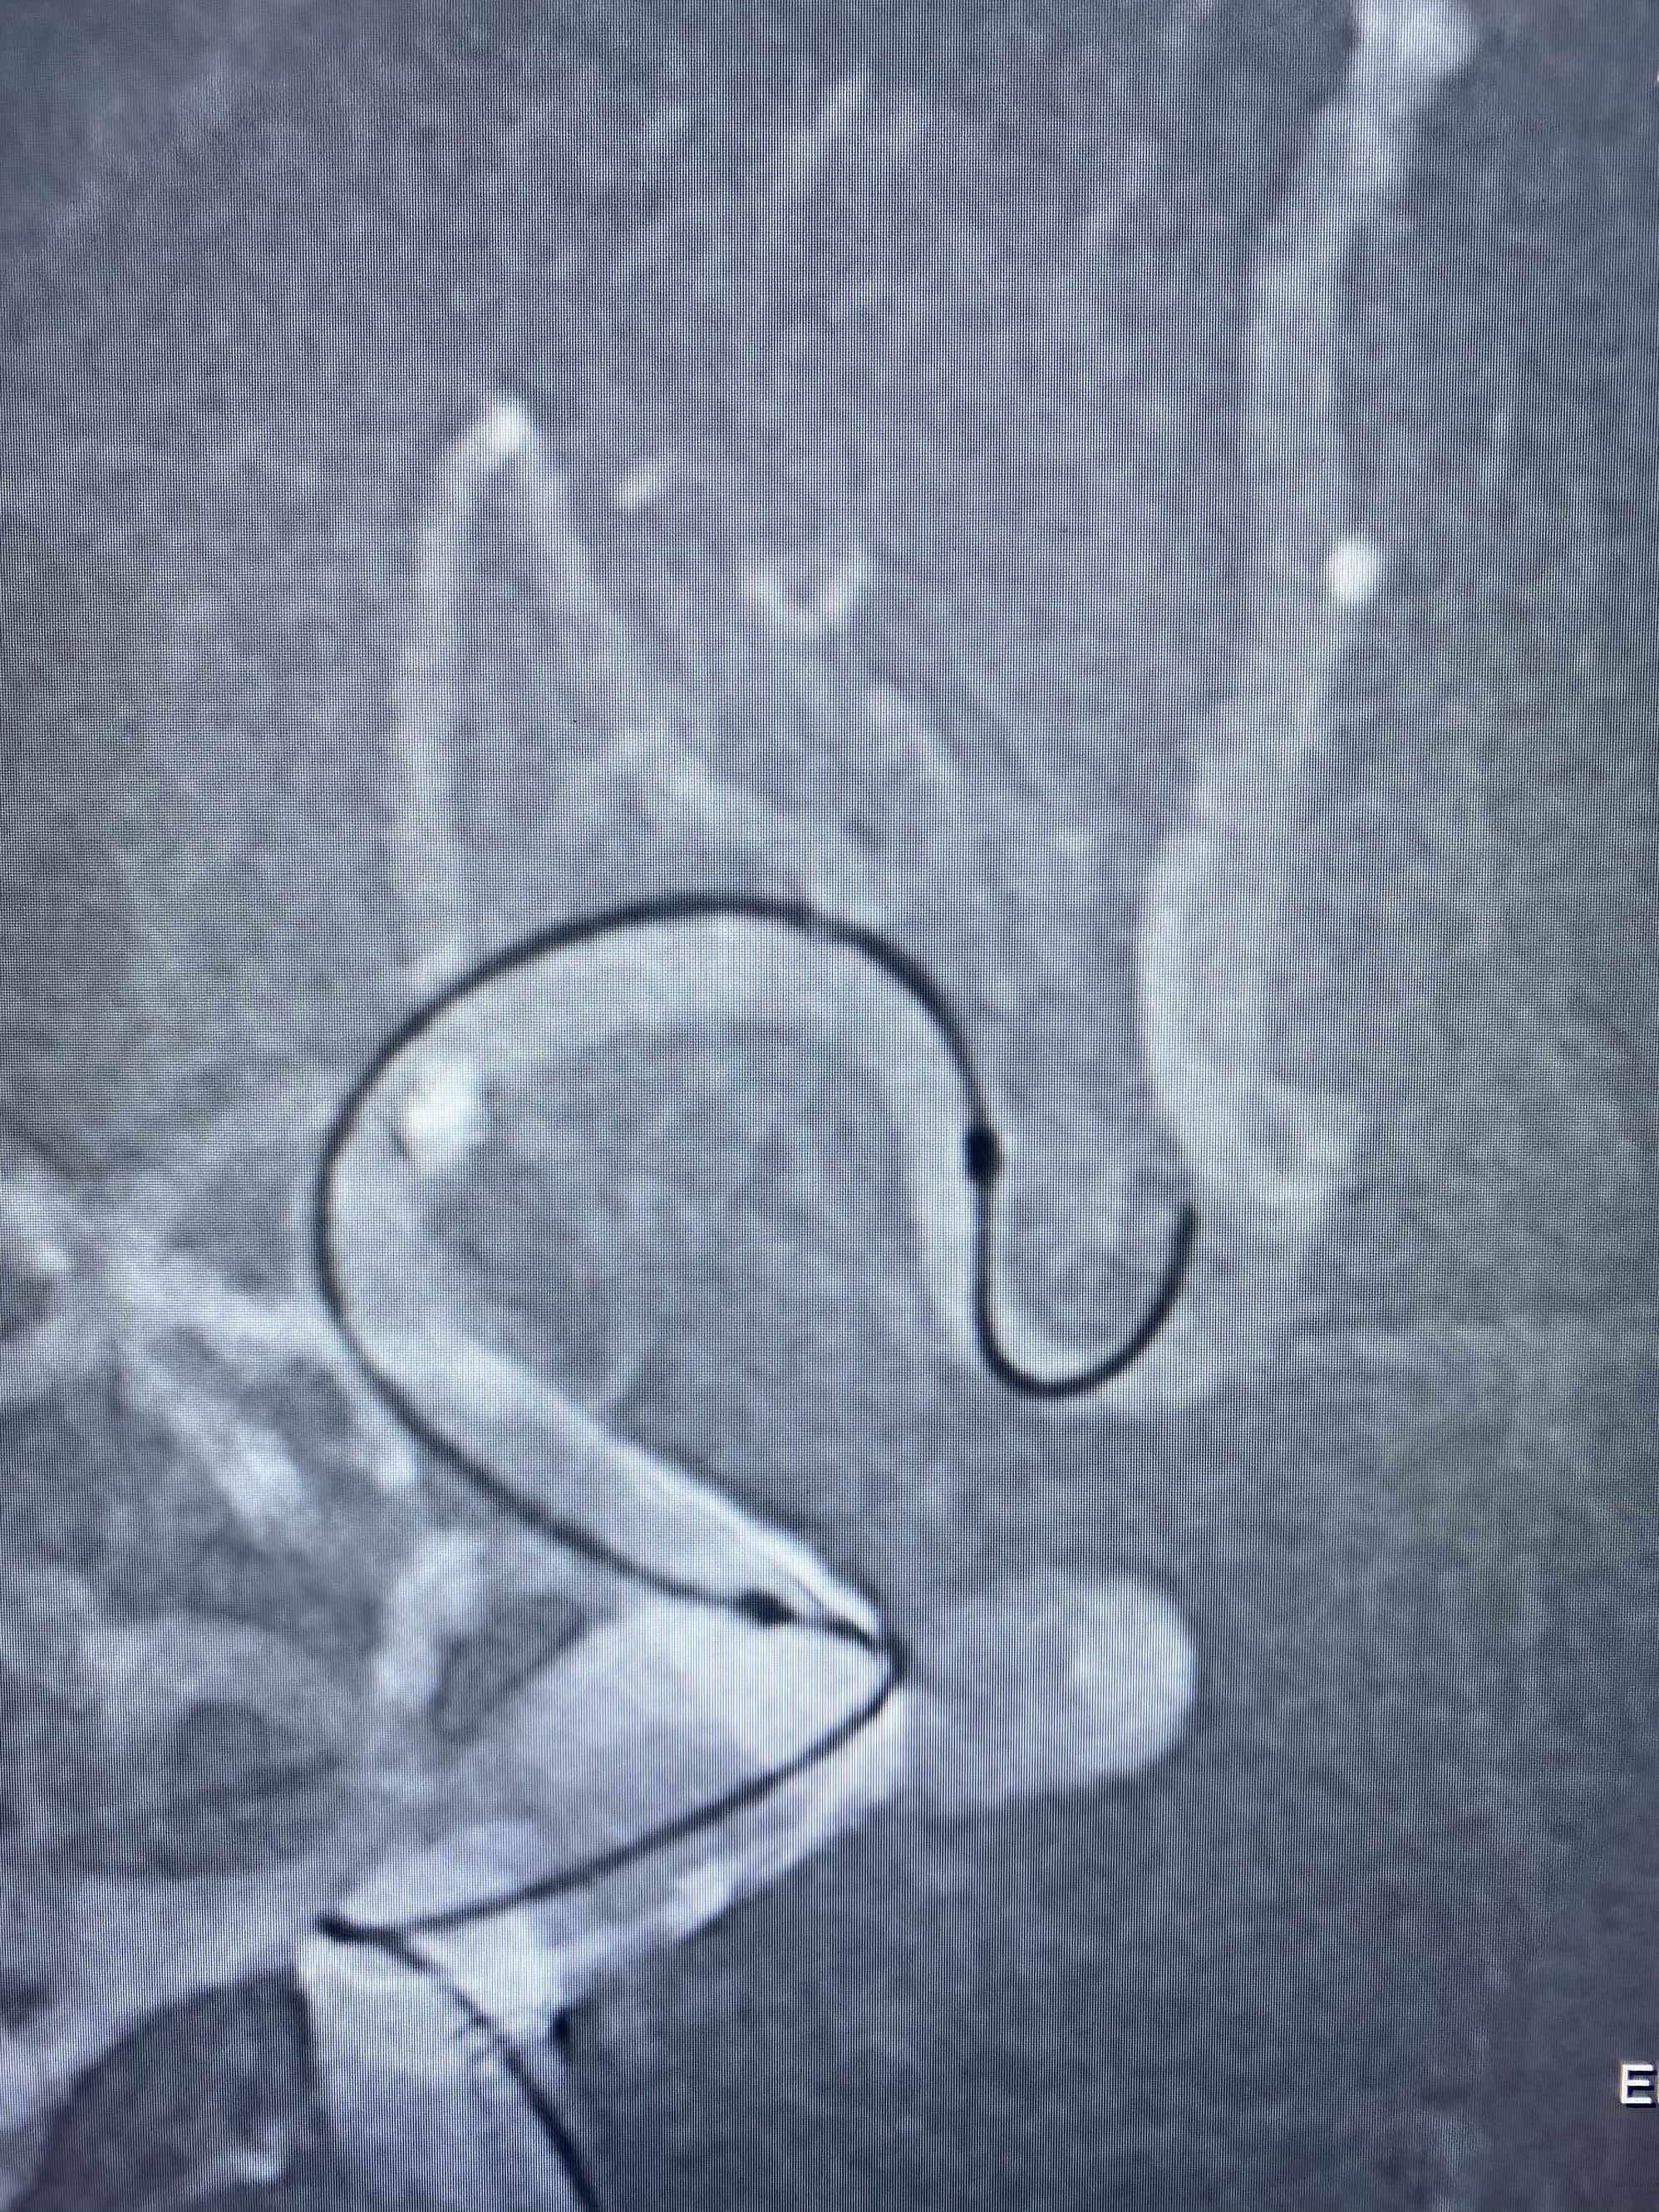

MLS,M79Y,sah,双侧MCA烟雾病,Heubner返动脉瘤,前交通段开窗,细支发出Heubner返动脉,瘤颈细长,瘤颈口比微导管细,弹簧圈2mmx3cm“隔山打牛”填塞治愈,Heubner返动脉保留。